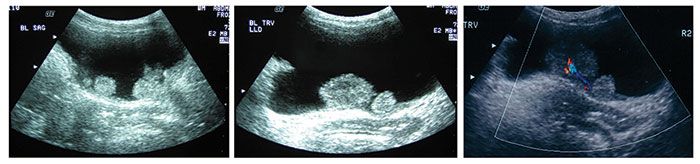

Figure 1. Ultrasonography detected multiple polypoid masses in the bladder of a 65-year-old HIV-infected woman. The largest mass measured 2.4 × 2.1 × 2.9 cm. Pathological examination revealed that a low-grade urothelial carcinoma had invaded the submucosa.

The patient reported recurrent right upper quadrant pain in 2003 but was asymptomatic until 2004, when she presented to the emergency department with persistent abdominal pain and associated difficulty in voiding (the results of urinalysis were not available). Abdominal ultrasonography showed multiple polypoid bladder masses with tumors on the bladder neck and posterior and lateral bladder walls (Figure 1). Two months later, a large (5-cm) mass situated on the trigone and multiple tumors on the bladder neck and posterior and lateral bladder walls were removed through transurethral resection.

Pathological examination revealed that a low-grade, T1 urothelial carcinoma had invaded the submucosa. The patient's CD4+ cell count was 305/μL, and her HIV RNA level was 10,000 copies/mL (the antiretroviral therapy had been discontinued 2 months before laboratory testing). She had been a heavy smoker in the past and smoked 2 or 3 cigarettes a day at the time of diagnosis.